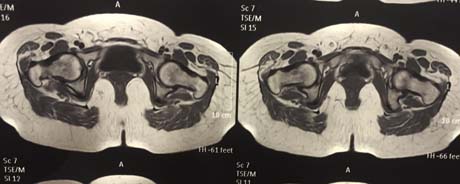

Magnetic resonance imaging of the hip after 5 months post-op and the injection of stem cells. Osteonecrosis of the femoral head has subsided completely. The patient is fully cured.

After surgery on the patients right hip the symptoms began to subside immediately. The patient gradually weight bearing the right limb, and five months after it is fully functional without any pain and stiffness in the hip joint.

The method of treatment applied to a patient is the modern conjunction surgery and cell therapy (stem cell therapy), which combination tends to replace older surgical methods are highly invasive (vascularized fibula autograft). This new method is one of the minimally invasive surgery which means minimal postoperative pain, quick recovery and return to social and sporting activities.